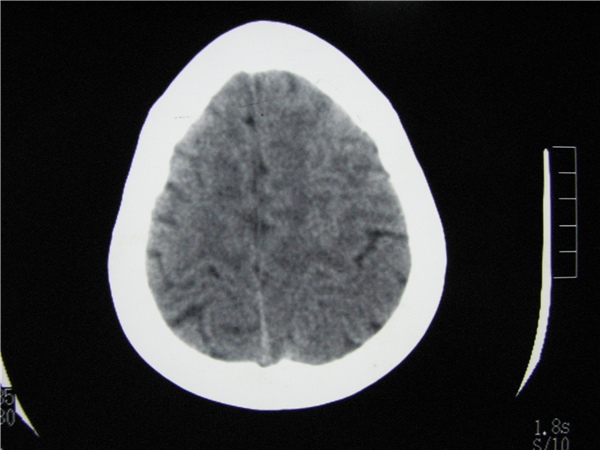

m 15y 头痛,以前有外伤史请老师看看除了囊肿还有别的吗?

蛛网膜囊肿。眼拙,看不出别的,倒是看到了双侧大脑中动脉影,类似“致密动脉征”。

双侧侧裂池和纵裂池近前颅窝蛛网膜囊肿。

无明显占位及负占位效应,考虑软化灶并脑室穿通畸形囊肿、局限性脑萎缩

蛛网膜囊肿,不能除外脑穿通畸形,支持。

谁把这病灶和表皮样囊肿鉴别哈